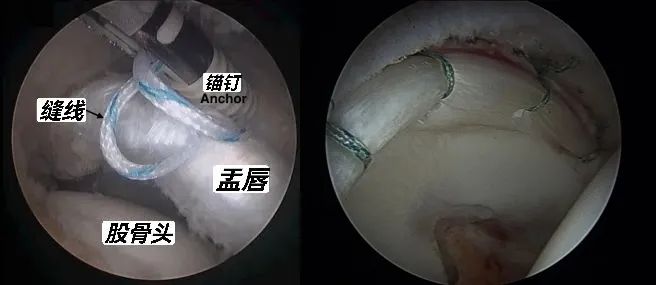

X线透视下建立髋关节镜各手术入路①髋盂唇缝合

探查盂唇,确认撕裂。

在盂唇止点的髋臼处进行新鲜化处理。

在盂唇原附着点钻孔,植入带缝线的锚钉,进行缝合固定。

髋盂唇缝合术步骤

髋盂唇缝合示意图及缝合完毕后情况②髋圆韧带清理